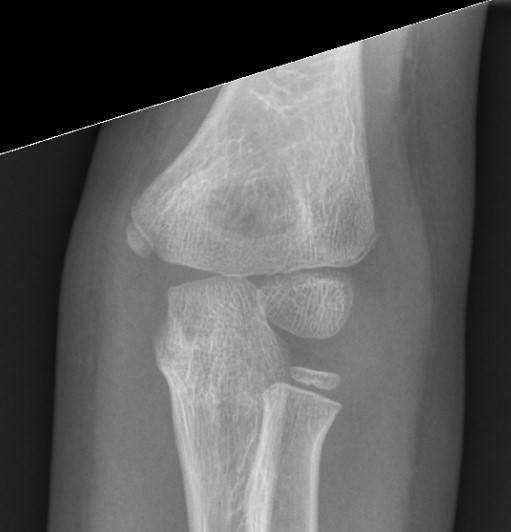

Internal oblique xray

Edmonds et al J Paediatr Orthop 2021

- 140 cases lateral condyle fracture treated non operatively

- displacement < 1.2 mm on internal oblique had failure rate of 58%

- displacement > 1.2 mm on internal oblique had failure rate of 1%

Kurtulmus et al Eur J Orthop Surg Traumatol 2014

- 27 patients with < 2 mm displacement on AP view

- 16 found to have > 2 mm displacement on subsequent internal oblique view